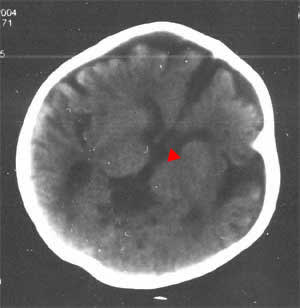

没想到在胼胝体发育不良上,大家还有这么大的分歧。红尖头所指为胼胝体发育不良,请大家指教

箭头所指应该是透明隔间腔,而不是胼胝体。

箭头所指为胼胝体膝部,同意胼胝体发育不良的诊断。

那为什么几个层面都没有看到胼胝体啊?[emb10]

以下是引用91616lyt在2004-3-25 22:36:02的发言:[br]箭头所指应该是透明隔间腔,而不是胼胝体。

那胼胝体膝部在什么地方?能否标出来